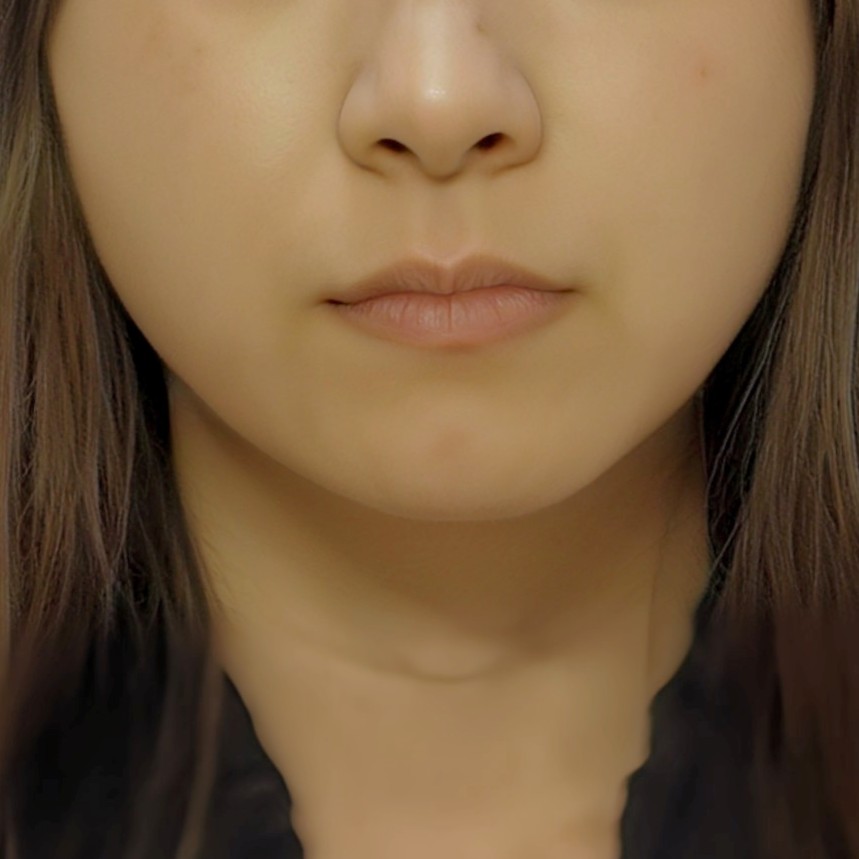

治療開始時

顔貌写真

顔貌写真